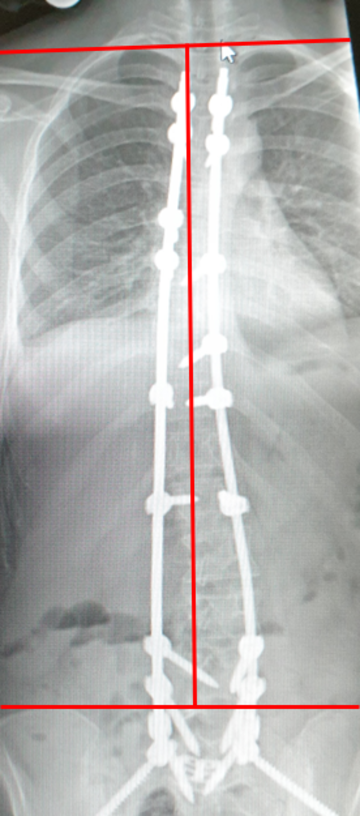

Vor der Operation

Schnell voranschreitende doppelbogige Skoliose bei einem 17 Jahre alten Mädchen. Beachten Sie die Beckenverkippung (rote Linie) und zusammenstehenden Rippen (roter Pfeil).

OP-Ergebnis

Harmonisch stehende korrigierte Wirbelsäule mit einer leichten Schultererhöhung, die sich unter Physiotherapie normalisiert hat (Rote Striche). Das Becken steht wieder gerade. Die Rippenstellung hat sich normalisiert.